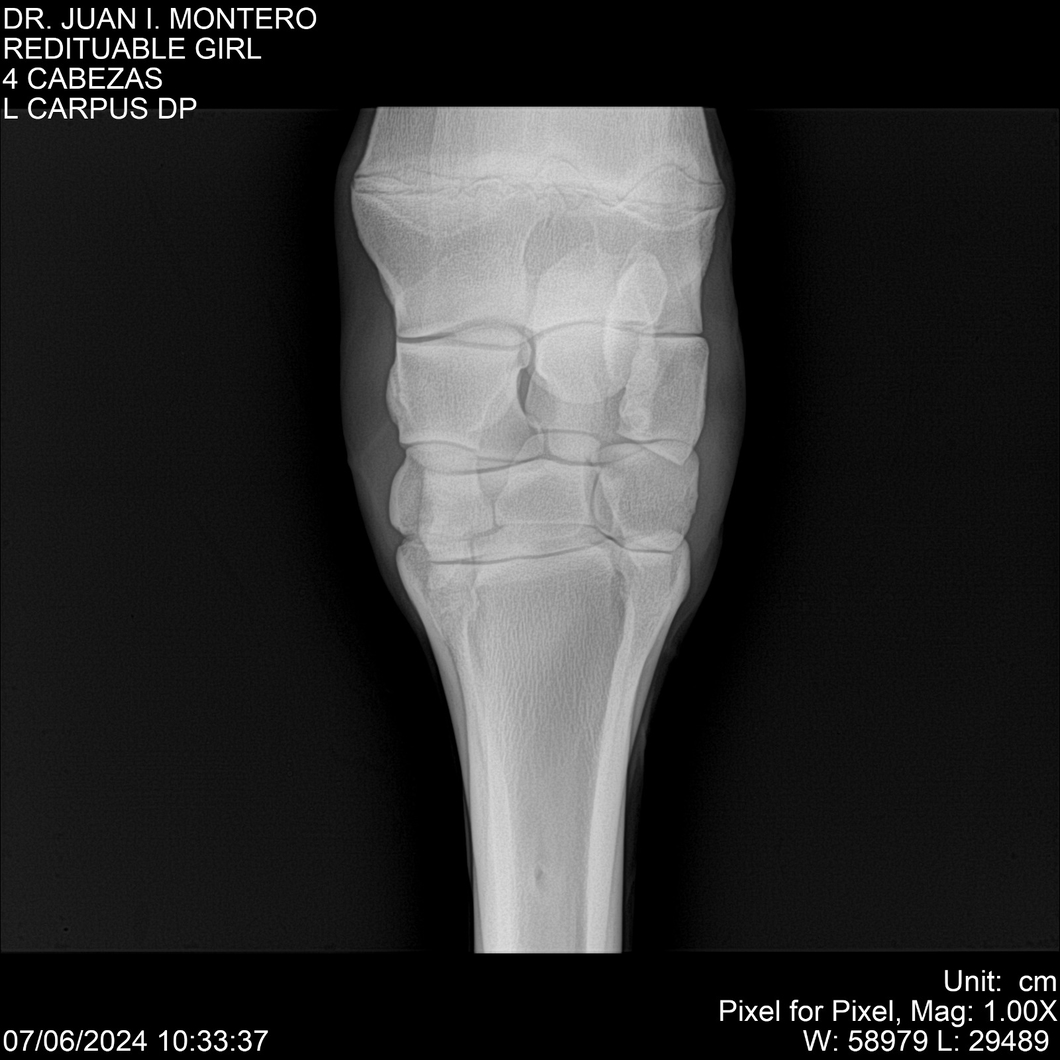

LOTE 19, REDITUABLE GIRL Lote Anterior Volver al remate Lote Siguiente Ficha Contacto Montevideo - Ficha del Lote Identificador: #281096 Categoría: Yeguarizos Montevideo - 79 Visualizaciones ClicData Contacto Empresa: Abelenda N. R., Walter Hugo Nombre*: Teléfono* : E-mail* : Mensaje Enviar Registrese gratis Este contenido Exclusivo está disponible sólo para usuarios registrados Ingresar